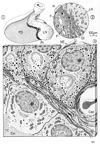

神経葉;神経部(下垂体の)Neural lobe of pituitary gland; Pars nervosa of pituitary gland(Lobus nervosus neurohypophysis; Pars nervosa neurohypophysis)

神経葉;神経部(下垂体の)【しんけいよう;しんけいぶ(かすいたいの)】 True posterior lobe of the pituitary gland.